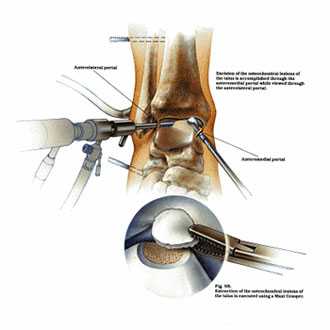

Благодаря современному оснащению нашей клиники сегодня мы можем отказаться от травматичных открытых операций на голеностопном суставе. На замену им пришла артроскопия.

Суть вмешательства проста. Через небольшие разрезы врач вводит в полость сустава специальную трубку, снабженную видеокамерой. Камера дает необходимый обзор, позволяя с высокой точностью проводить операцию. В ходе артроскопии медик либо удаляет некротизированный кусок костной ткани, чтобы он не доставлял человеку неудобств, либо, если некроз не окончательно поразил участок кости, крепит доставляющую неудобства часть к основному массиву с помощью специальных скобок или винтов.

Артроскопия, метод выбора для пациентов с рассекающим остеохондритом. Операция менее травматична, восстановление после нее проходит легче и быстрее.